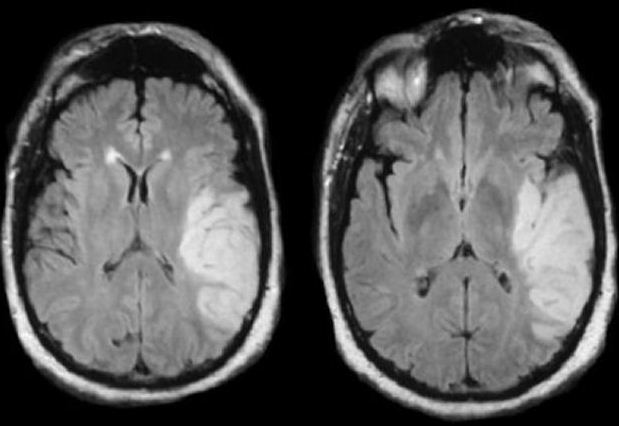

Image on left is SWI

Image on right is DWI

Stroke Syndrome:

In a right-handed patient:

Right superior division MCA